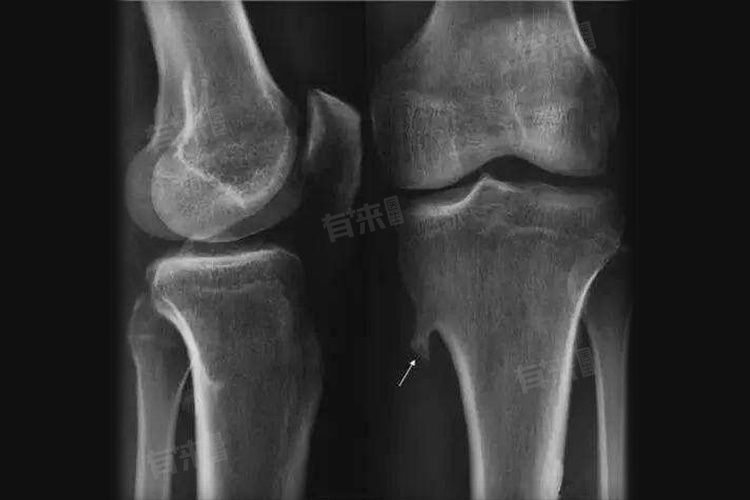

1、股骨远端:股骨是人体最长的管状骨,股骨远端靠近膝关节,此处骨骺生长活跃,代谢旺盛,为骨肿瘤的发生提供了条件。骨肉瘤等恶性肿瘤在股骨远端较为高发,初期患者可能感到膝关节上方隐痛,活动后加重,容易被误认为是生长痛或运动损伤。随着病情发展,疼痛加剧,局部还可能出现肿胀、肿块,影响膝关节活动。

2、胫骨近端:胫骨近端同样是儿童骨肿瘤的常见发病部位。该部位不仅生长发育迅速,而且日常活动中承受较大压力,易受机械应力刺激。尤因肉瘤在胫骨近端时有发生,肿瘤生长会破坏骨组织,导致局部疼痛、肿胀,还可能引起发热、乏力等全身症状,严重影响患儿的身体健康和生活质量。

- 影像学检查:X线检查可初步观察骨骼形态、结构变化,判断有无骨质破坏、骨膜反应等。CT检查能更清晰地显示肿瘤的范围、与周围骨骼的关系,以及有无骨质增生、钙化。MRI检查则擅长显示软组织与骨骼的关系,能准确判断肿瘤侵犯的程度,是否累及骨髓、血管和神经。骨扫描可检测全身骨骼的代谢情况,发现潜在的肿瘤病灶,尤其适用于查找骨转移瘤。